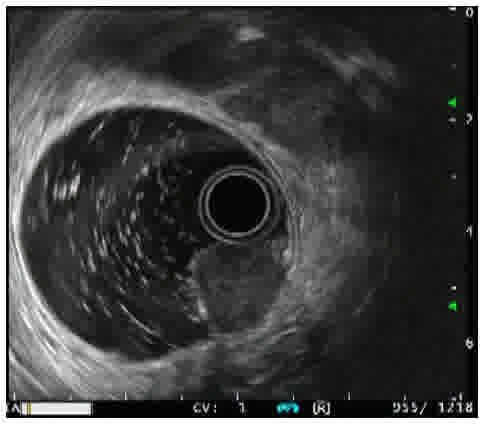

A 25-year-old man presented to Kangwon National University Hospital (Chuncheon, South Korea) in March 2017, subsequent to suffering from acute diarrhea, fever, vomiting and abdominal pain for 3 days, in addition to 2 years of chronic anal bleeding. A physical examination revealed mild abdominal tenderness in his right lower quadrant. A digital rectal examination indicated a 1-cm, hard, smooth-surfaced and palpable mass in the distal rectum. A sigmoidoscopy was performed to evaluate the palpable distal rectal lesion; the terminal ileum was reached following the removal of fecal material, which revealed edematous hyperemic mucosa of the terminal ileum and an oval-shaped subepithelial tumor (SET) with normal surface mucosa in the distal rectum. The colonic mucosa was otherwise intact, without inflammation or bleeding (Fig. 1). A transrectal endoscopic ultrasound (EUS) for distal rectal SET revealed a 1.5-cm, ovoid, hypoechoic lesion originating from the second layer, which corresponded to the deep mucosa (Fig. 2).

Figure 2.

Transrectal endoscopic ultrasound revealing a 1.5-cm, ovoid, hypoechoic, subepithelial lesion with smooth margins originating from the second layer, which corresponds to deep mucosal layer.